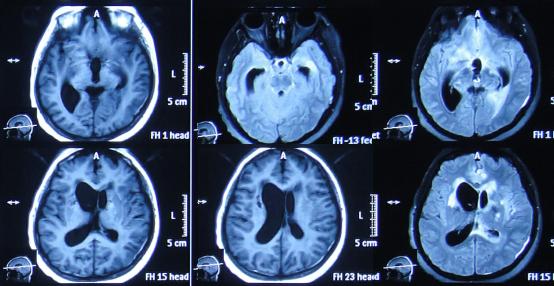

患者于2015年7月31日,无明显诱因突发头痛发热症状,体温升高至38.6℃,因自行服药3天后无改善即2015年8月3日,就诊并住入第1家的位于四川省成都市某军医院的神经内科,查头MRI示“右侧小脑半球结节影,环性强化”(图-1)。

图-1:2015年8月3日头部MRI

经头孢哌酮舒巴坦抗感染治疗1周后即2015年8月9日,仍间断头痛,发热有下降,但仍反复,但患者意识反变差,表情也变淡漠,查头部CT(图-2)。

图-2:2015年8月9日头部CT